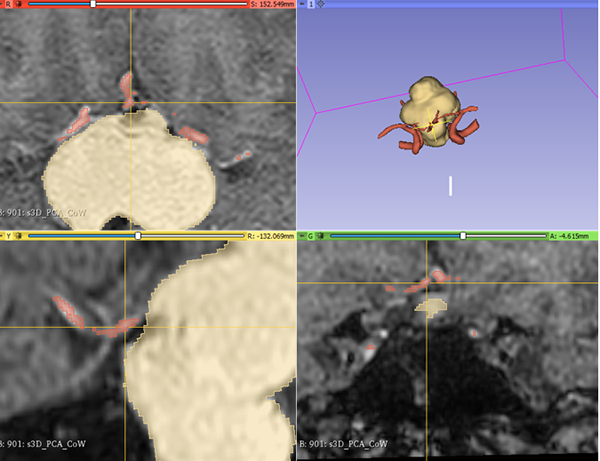

En RM de cerebro se observa lesión espacio ocupante selar-supraselar con aspecto multilobulado que invade cisterna interpeduncular y desplaza estructuras del tercer ventrículo. La misma es hiperintensa espontáneamente en T1 con captación heterogénea de contraste, hiperintensa en T2 (Figura 1). En secuencia de angioresonancia se observa su relación medial respecto a arterias carótidas no comprometiendo las mismas (Figura 2). A partir de éstas imágenes obtenidas en resonador 3 Tesla, en el Departamento de Innovación Tecnológica del Instituto Cardiológico de la Ciudad de Corrientes se realizó un proceso de segmentación de las distintas partes de interés (tumor, arterias, nervios ópticos y globos oculares). Para esto se utilizó el software “Open Source 3D Slicer (versión 4.11)” (Figura 3). Una vez segmentadas las regiones de interés, se realizó, mediante una impresora 3D “MAX” de la empresa Creatbot, un modelo 3D cuyos materiales consistieron en poliácido láctico (PLA) y poliuretano termoplástico (Figuras 4 y 5). Con el mismo, se realizó la planificación del abordaje quirúrgico.

Figura 3: Segmentación de las regiones de interés mediante Software “Open Source 3D Slicer (versión 4.11)”